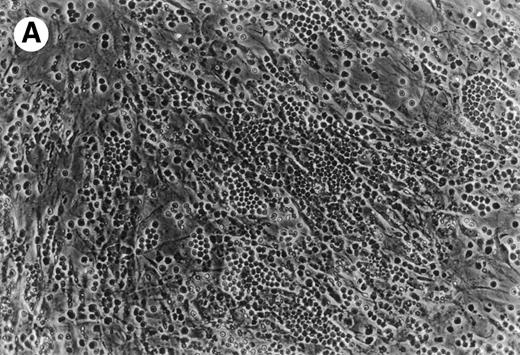

Coculture of CLL cells with the murine-marrow-stroma cell-line, M2-10B4, results in spontaneous migration of CLL cells into the stromal cell layer. This in vitro phenomenon termed pseudoemperipolesis is characterized by the dark appearance of cells that have migrated into the same focal plane as the stromal cells, whereas the more superficial, nonmigrated cells remain refractile (Fig 6).30 Time-course experiments showed that pseudoemperipolesis of CLL cells mostly occurred within the first 2 hours of coculture (Fig 7B). Titration of the input CLL cell numbers showed that concentrations above 1 × 107 cells per 24 well plate did not significantly increase the number of migrated cells (Fig 7C). A 2-hour assay with 1 × 107 input cells was found to be the optimal condition for this assay and hence was used in subsequent inhibition studies. Under these conditions, an average of 7.4% ± 3.7% (mean ± SD) of input CLL cells from 6 different patients migrated into the stromal layer. For comparison, we assessed the migration of Nalm-6 cells and found that 6.9% ± 0.5% (mean ± SE of duplicate tests) of the input cells migrated into the stromal layer under the same experimental conditions.

(A) Representative phase contrast photomicrograph of pseudoemperipolesis of CLL B cells after 2-hour culture on the heterologous murine stromal cell line, M2-10B4. Cells that had not migrated beneath the stromal cells washed off, and the stromal cell layer containing the migrated CLL cells was photographed (200x magnification). Pseudoemperipolesis is characterized by the dark appearance of lymphocytes that have migrated into the same focal plane as the stromal cells. (B) For comparison, this photomicrograph shows reduced pseudoemperipolesis after pretreatment of CLL cells with pertussis toxin.